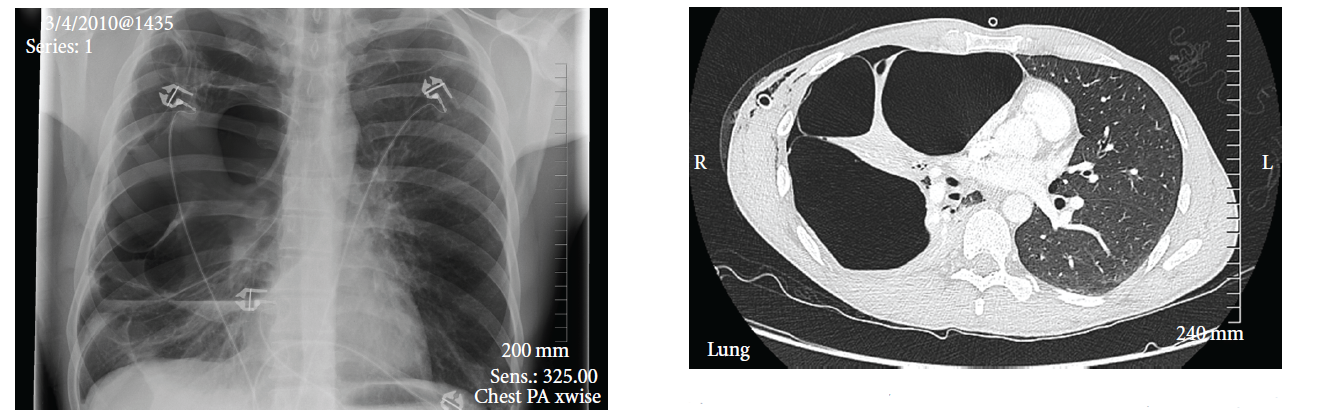

If you have persistent symptoms of emphysema, your doctor might recommend some tests to understand your lung health, including X-rays and computerized tomography (CT) scans, which can reveal the presence of blebs and bullae.

In most pneumothorax cases, a chest X-ray is the first-line diagnostic tool. Doctors may also order an ultrasound to identify pneumothorax. For more detailed images, a CT scan may be necessary.

CT scans use multiple X-rays from different angles and computer-processed combinations to produce high-quality images of the pleural space and any blebs or bullae. Those images can determine the size and location of a bleb or bulla. Technicians may also use computed tomography to help with the placement of a tube thoracostomy.